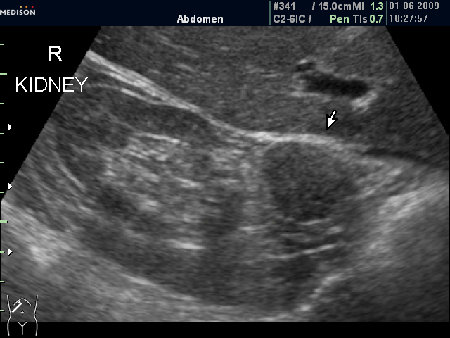

Женщина 72 лет. При УЗИ выявлены два аваскулярные образования: в нижнем полюсе правой почки и у верхнего полюса почки.

Уникальность случая в том, что эти изменения - БЕЗ ДИНАМИКИ с 2005 года.

Опухоль почки?

Без допплера явно опухоль почки